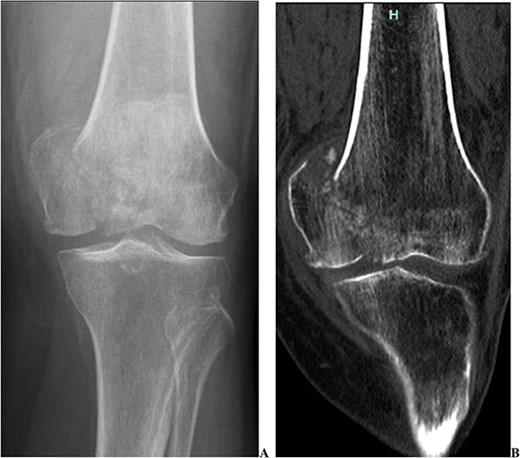

We present the case of a 76 year old Hispanic female previously managed for tri-compartmental osteoarthritis and lateral condyle insufficiency fracture of the left knee. She was being managed conservatively; however, the pain began to affect her well-being and activities of daily living (ADL). Most recently the patient suffered a mechanical ground level fall resulting in an ipsi-lateral medial condyle fracture as seen in Fig. 1. Single staged left knee medial condyle ORIF and CCK arthroplasty through a medial para-patellar approach was performed. The medial condyle fracture was reduced and stabilized using a 5-hole distal fibula locking plate in buttress mode. After fracture stabilization, a CCK arthroplasty was performed. Immediate post-operative imaging is seen in Fig. 2. Intra-operative photos are demonstrated in Fig. 3. The patient was made non-weight bearing for 2 weeks followed by weight bearing as tolerated (WBAT). An early weight bearing protocol was used given the majority of forces during ambulation would be placed through the total knee implant and not place significant stress on the medial condyle ORIF. At 3 months post-operatively, the patient obtained 0–120° range of motion (ROM) and was freely WBAT. At 8 weeks, however, the patient required a manipulation under anesthesia for regressing to 0–95° ROM. Figure 4 demonstrates intra-operative images of the manipulation. At 3 years follow up, her ROM was 5–95 with good strength without any further complication or subsequent procedures. Three years post-operatively the patient reported improved function with ADLs, significantly improved pain, and better mental health.

Two pre-operative injury images demonstrating the acute medial condyle distal femur fracture of the left knee. In addition to the acute fracture, one can appreciate the pre-existing osteoarthritis. (A) Radiograph demonstrating a large displaced medial condyle fracture. (B) CT scan re-demonstrating the acute medial condyle fractures.